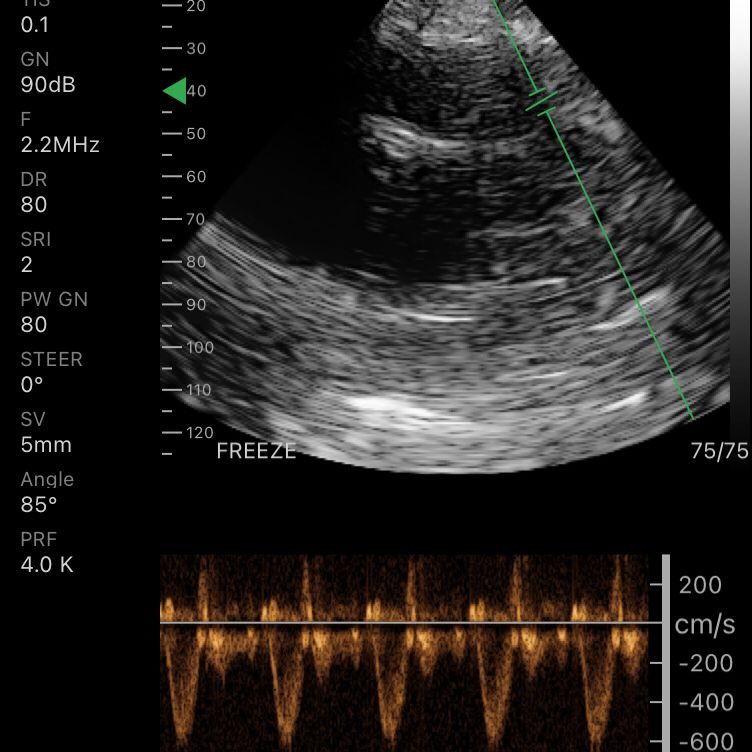

Modos de escaneo: B, B/M, Color, PW

Profundidad de pantalla: 90 – 190 mm

Velocidad de imagen: 24 fps

Exámenes básicos y control de flujo cardíaco o vascular en entornos clínicos y extrahospitalarios.